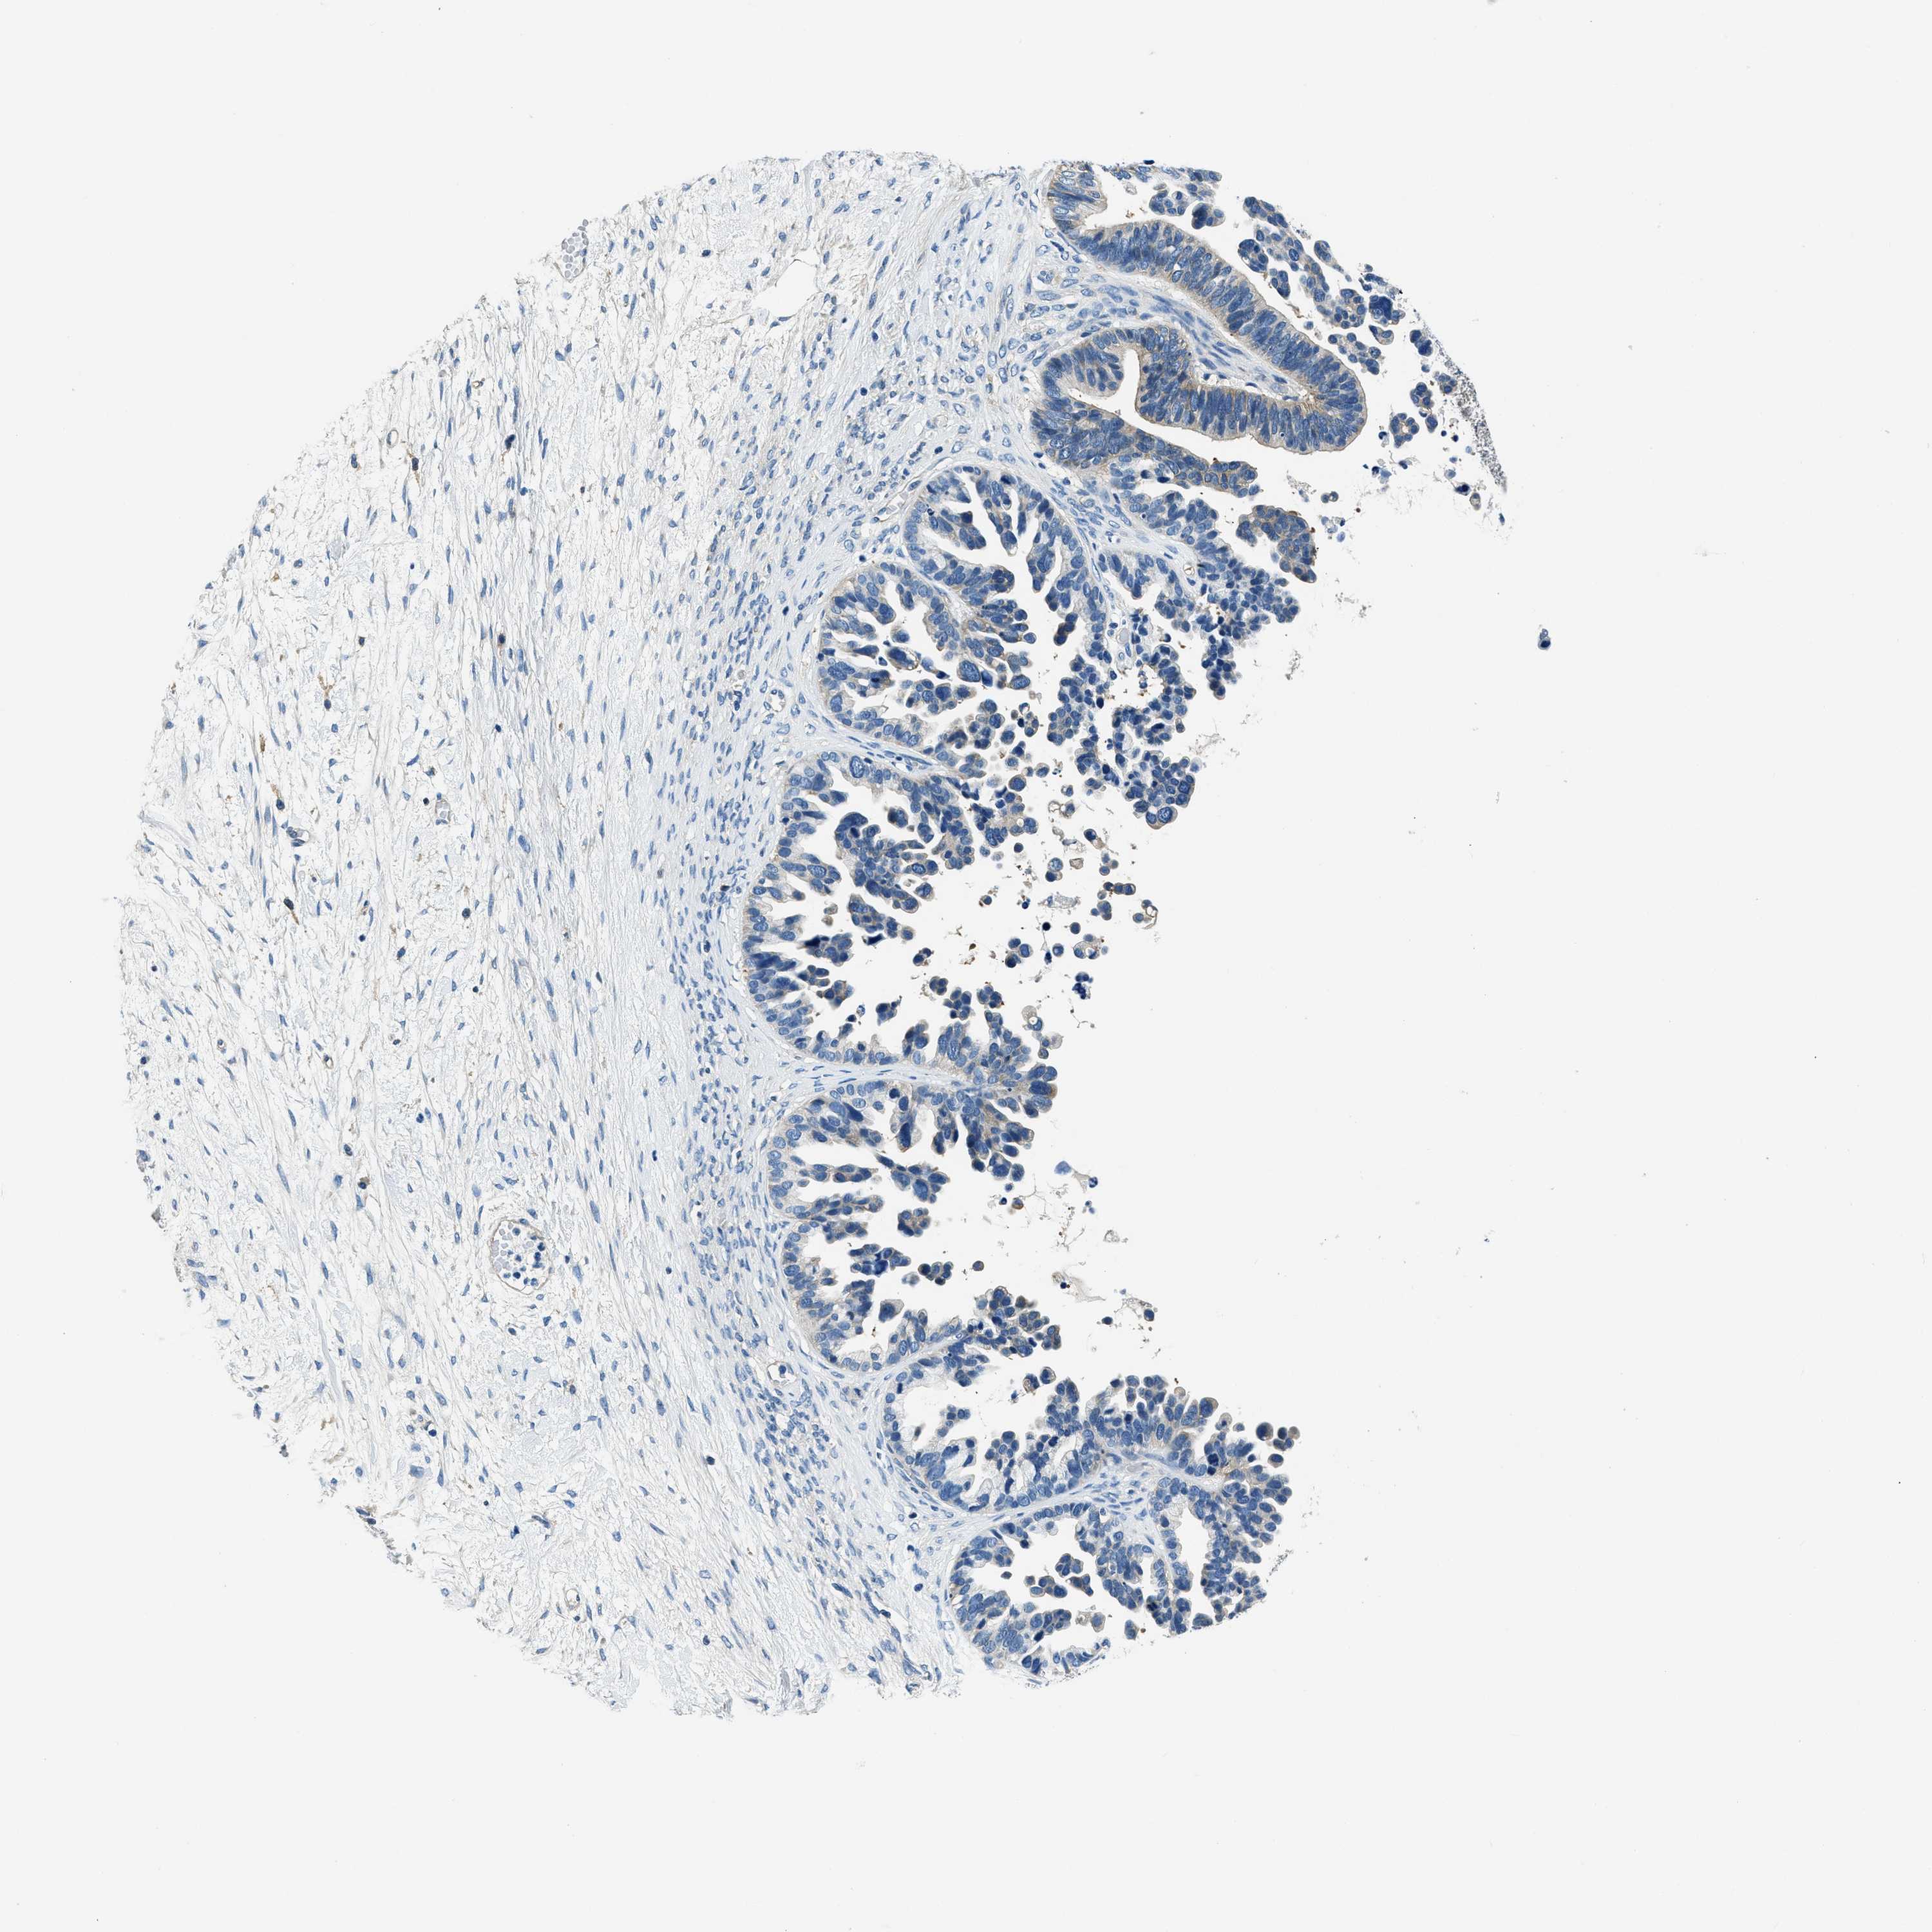

OVARIAN CANCER - Protein expressioni

A mouse-over function shows sample information and annotation data. Click on an image to view it in a full screen mode. Samples can be filtered based on level of antibody staining by selecting one or several of the following categories: high, medium, low and not detected. The assay and annotation is described here.

Note that samples used for immunohistochemistry by the Human Protein Atlas do not correspond to samples in the TCGA dataset.

Antibody stainingi

Antibody staining in the annotated cell types in the current human tissue is reported as not detected, low, medium, or high, based on conventional immunohistochemistry profiling in selected tissues. This score is based on the combination of the staining intensity and fraction of stained cells.

Each image is clickable and will lead to virtual microscopy that enables deeper exploration of all samples and also displays staining intensity scores, fraction scores and subcellular localization as well as patient and tissue information for each sample.

Antibody HPA018116

Staining

High

Medium

Low

Not detected

Intensity

Strong

Moderate

Weak

Negative

Quantity

>75%

75%-25%

<25%

None

Location

Nuclear

Cytoplasmic/membranous

Cytoplasmic/membranous,nuclear

Cystadenocarcinoma, serous, NOS

Carcinoma, endometroid

Cystadenocarcinoma, mucinous, NOS

Carcinoma, NOS